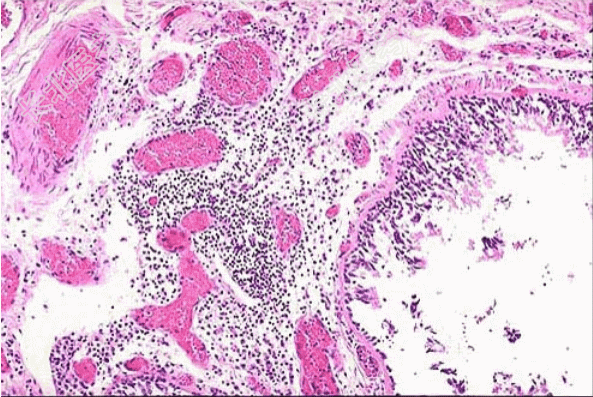

- [材料题] 患者,男,55岁,每年冬春季节均会出现反复发作的咳嗽、咳痰等症状,至少持续3个月以上。胸片示肺纹理增粗,紊乱。

- 简答题1、纤支镜取活检镜下如图所示,该患者正确的诊断是?